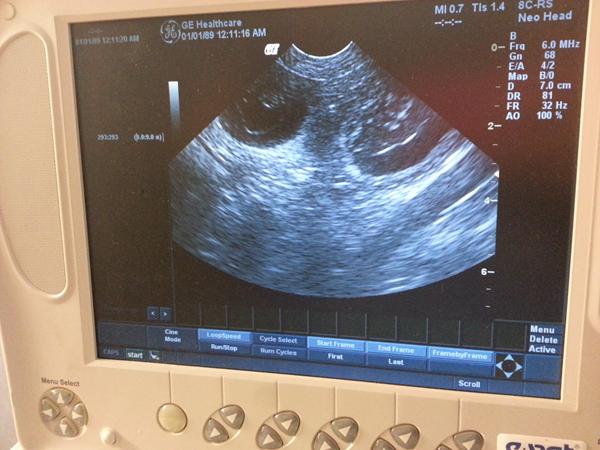

Eccola er i dag blevet scannet, og sørme om der ikke var sådan nogle små bobler, dyrlæge kunne tælle 6 meget præcist men hun regner med flere, så nu er der bare og vente og vente og så vente lidt mere....